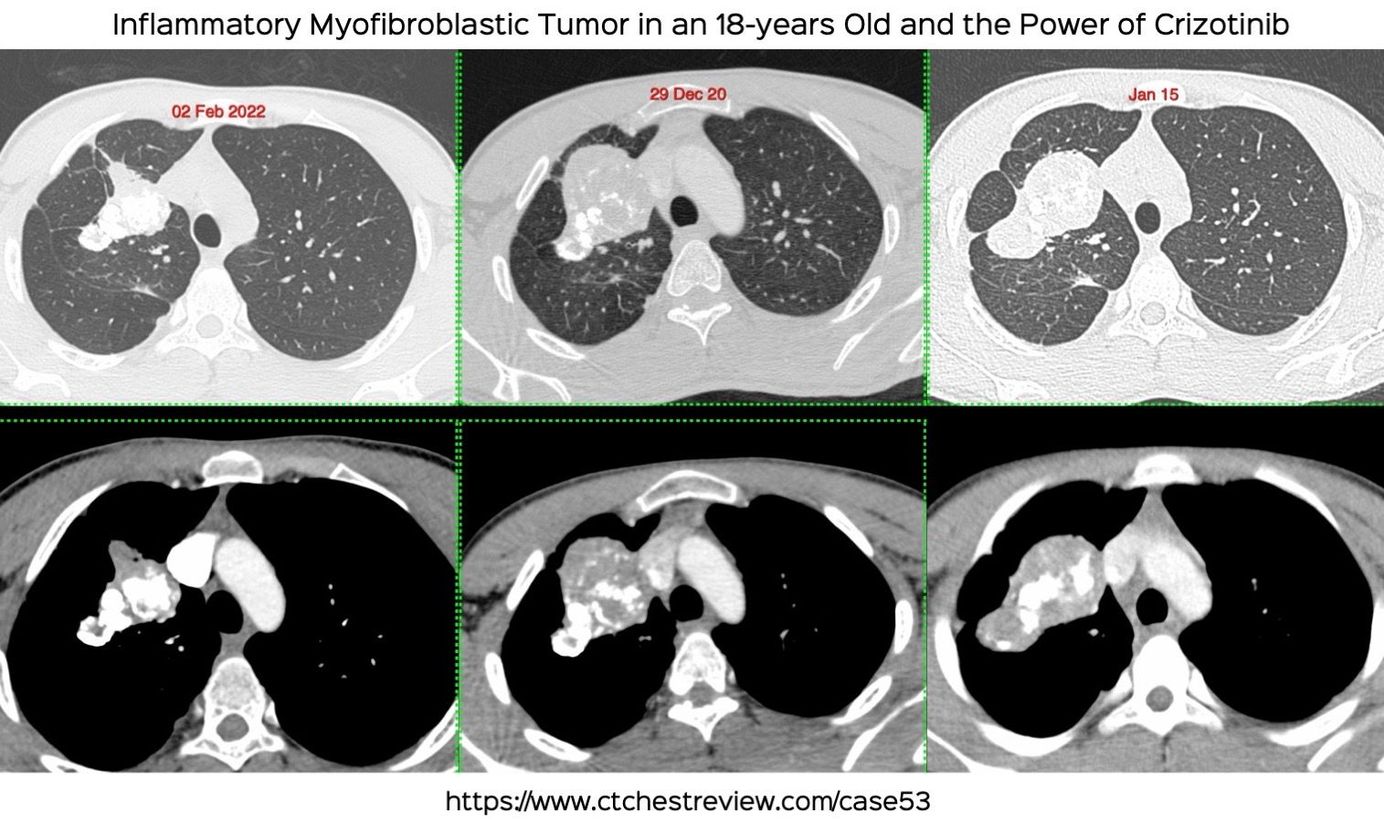

This 18-years old presented in 2015 with a lung mass that on biopsy was diagnosed as "inflammatory pseudotumor". Nothing was done and the patient re-presented in Dec 2020 with minimal symptoms. The mass had increased in size.